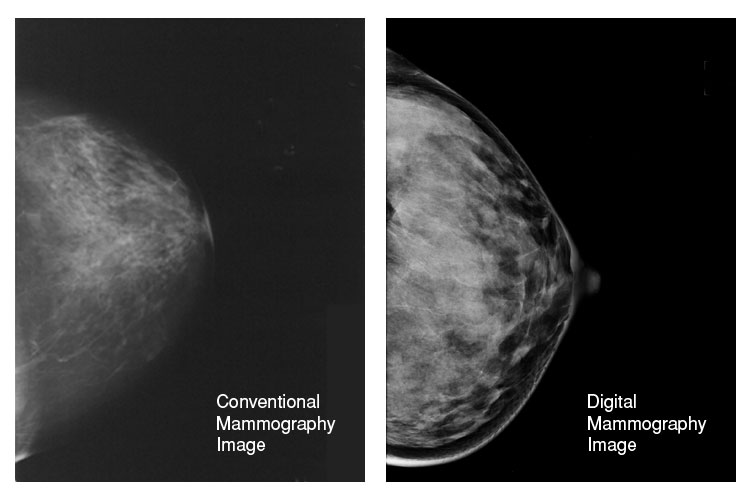

The Difference is Clear

The high-resolution of digital images allows radiologists to see more details and detect abnormalities by manipulating brightness, magnification, orientation and contrast.

Conventional Mammography Image (left) Digital Mammography Image (right)